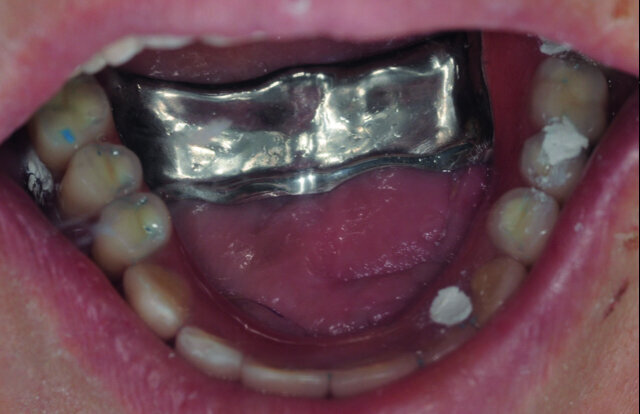

Cette technique est parfaitement codifiée et de nombreuses publications citent des taux de succès équivalents aux mises en charge différées.4–6 Cette mise en charge immédiate est finalisée par la pose, dans un délai de 2 à 5 jours après la mise en place des implants, d’un bridge transitoire vissé métal/résine. Ce bridge transitoire est l’élément fondamental du traitement. C’est un dispositif monobloc de forte rigidité, véritable fixateur externe qui réunit les implants.

En cas d’atrophie osseuse importante au maxillaire supérieur, l’armature comportera une entretoise palatine qui sera coupée à un an postop (Fig. 6a). Le vissage se fait toujours passivement et en cas de difficulté, des bagues usinées en titane sont collées secondairement dans l’intrados de l’armature. Le décollement des bagues de collage reste exceptionnel8 et facilement réparable : il suffit de nettoyer la bague et la logette puis de recoller.

Fig. 6a : Bridge maxillaire vissé avec une entretoise palatine.